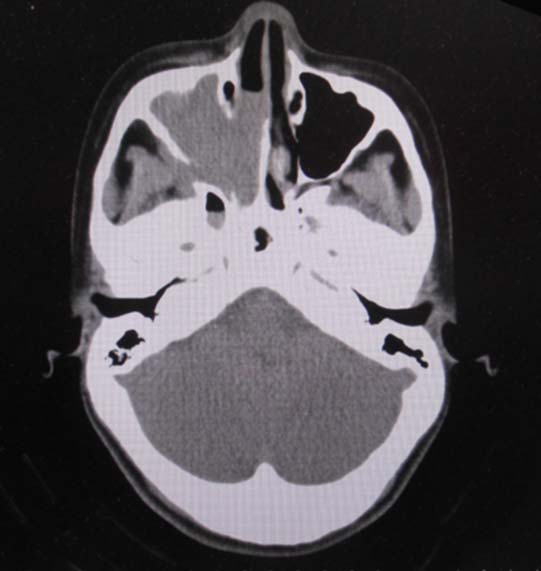

CT所見

CT画像および肺腫瘤生検組織